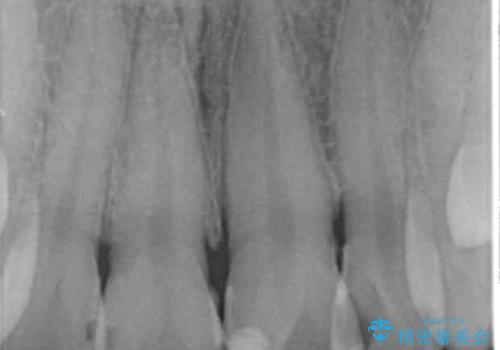

- 前歯をきれいにしたいとのご希望により来院された患者様です。

ご希望により、上の前歯4本のセラミッククラウンによる補綴治療を行いました。

- ¥572,000 (根管治療×1本、土台×1本、仮歯×4本、クラウン×4本) ※税込費用は治療当時の料金となります